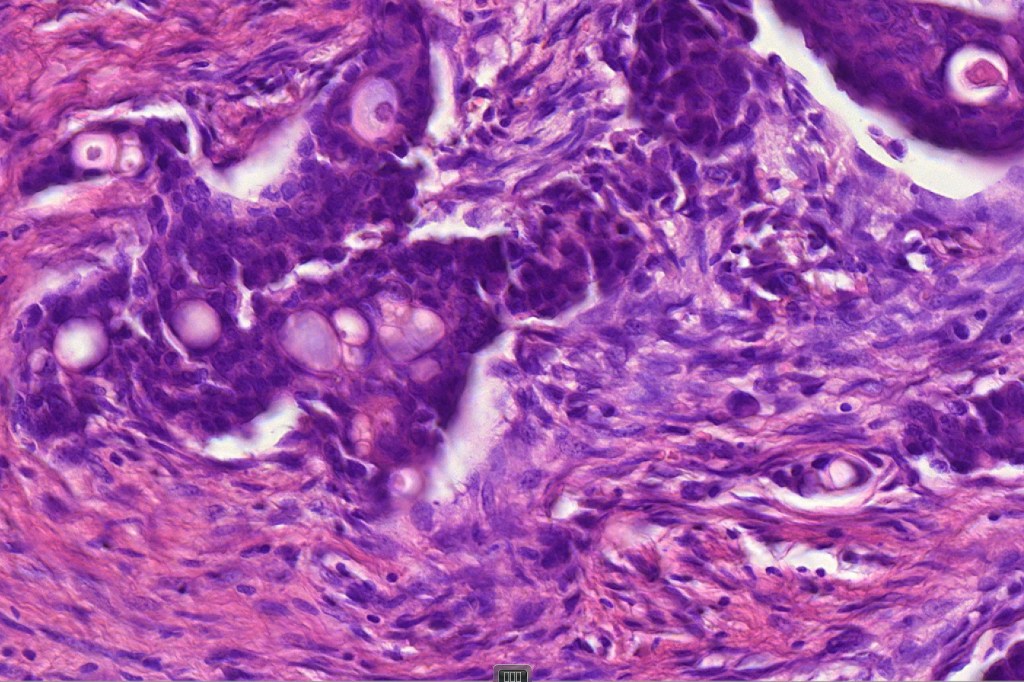

Histological features

•Poorly circumscribed tumor nodule with invasive border

•Variable glandular, tubular, papillary, tubulo-papillary, diffuse and solid growth patterns

•Large cells with vesicular nuclei and often prominent nucleoli

•Decapitation secretion

•Variable pleomorphism, mitotic activity & atypical mitoses

•Variable necrosis

•Variable lymphovascular involvement & perineural infiltration

•Exceptionally squamous, clear cell, granular cell and sebaceous differentiation

•Exceptionally single file and signet ring growth pattern (see signet ring cell carcinoma)